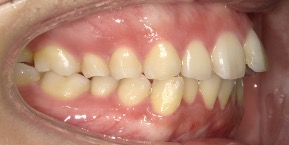

29歳女性のビフォーアフター

| 診断 | 叢生(デコボコがある状態)、過蓋咬合 |

| 治療方針 | インビザラインシステムにて主にIPR(歯と歯の間をわずかに削合してスペースを獲得する方法)を組み込んだ動的矯正治療を行い、叢生を改善後、保定を行う。臼歯部の咬合関係はプランの関係上維持して叢生と前歯部の咬合改善を目指した。 |

| 治療費 ※ | 60万4千円(診断、型取り、PMTC、保定装置を含む料金) |

| 治療期間 | 1年5か月 |

| リスク | 1日20時間以上マウスピースを使用できない場合、歯が動かない可能性がある。装着時や食事時に痛みを伴う。歯肉退縮や虫歯になるおそれがある。また、指導通りに装着できていない場合や適切なブラッシングが出来ていないとそのリスクが高くなる。歯根が短くなることがある。ごくまれに歯の神経が損傷してしまうことがある。過去にぶつけたり深い虫歯治療をしたことがあるとそのリスクはやや高くなる。矯正後には保定装置が必要。適切な使用ができない場合、後戻りの原因となる。将来的に歯並びが動いて再矯正が必要な場合がある。親知らずが正常に生えていない場合、その可能性がやや高くなる。 |